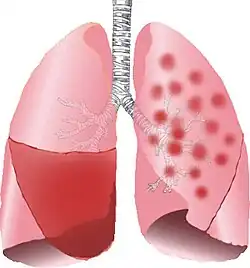

| Typical distribution of lobar pneumonia (left in image) and bronchopneumonia (right in image) | |

It is often contrasted with lobar pneumonia; but, in clinical practice, the types are difficult to apply, as the patterns usually overlap.[2] Bronchopneumonia (lobular) often leads to lobar pneumonia as the infection progresses. The same organism may cause one type of pneumonia in one patient, and another in a different patient.